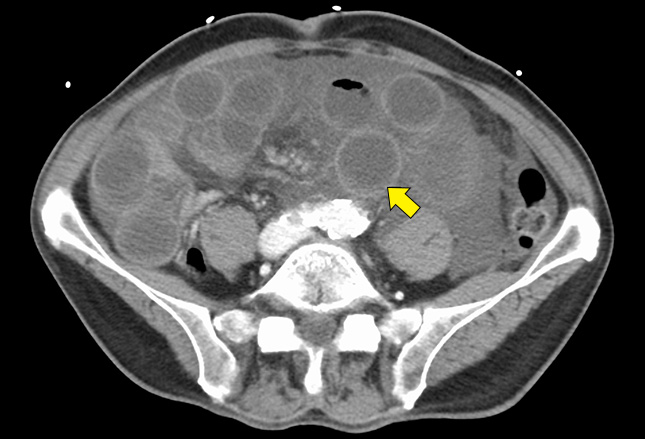

CT扫描描绘了肠系膜上静脉血栓形成的肠缺血。可见肠壁增厚(箭头)伴肠壁扩张。